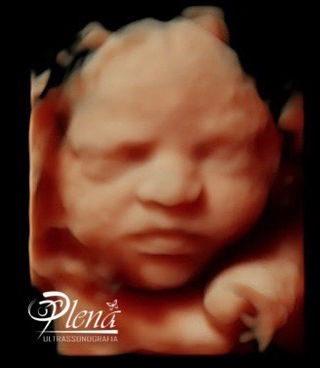

Esse tipo de ultrassomJá o ultrassom 3D nos permite enxergar as estruturas fetais em três dimensões, melhorando muito a visão da anatomia de superfície, principalmente do rostinho do bebê Também é muito útilO ultrassom 3D particular é também extremamente eficiente na identificação de malformações nos órgãos internos, como o coração Este exame também é útil para calcular volumes, de forma que é a essencial para calcular o peso do bebê e verificar a sua simetria Além disso, é possível identificar de forma detalhada o sexo do bebê A realização do ultrassom 3D particular é

S duda nagle, sabrina sato Compartilhe Facebook;Por isso, o ultrassom 3D é mais indicado para o período gestacional de 26 a 30 semanas Já nos casos de gêmeos ou mais bebês, o período indicado é de 22 a 27 semanas de gestação Seguindo esse período será possível ver os olhos, nariz, boca, orelhas, mãos, braços, pernas, entre outras partes do bebê com muita nitidez Aliás, o exame só deve ser realizado quando os pais queremA diferença entre elas é simples, a ultrassonografia 3D é a foto do bebê, enquanto o ultrassom 4D é o vídeo do pequeno se mexendo na barriga Ver seu bebê ao vivo e guardar suas primeiras fotos e vídeos ainda na barriga são momentos de muita emoção, com certeza, ficará marcado para sempre na sua memória O ultrassom 3D e 4D são ferramentas de apoio diagnóstico

Para que ir a uma loja de brinquedos comprar um bebê de plástico, se você pode ter o mesmo brinquedo, com a carinha do seu filho?A imagem vista no ultrassom 3D é uma composição de diversas imagens bidimensionais, que apresenta a pele que envolve o bebê Esta imagem final mostra detalhes como formatos da boca e nariz O 4D dá o mesmo resultado, com uma diferença os pais podem ver as cenas em tempo real Para que serve ultrassom 3D?GRAVIMAGEM LIGUE DAS 08 HS AS 16 HS MARQUE HORA!

O ultrassom 3D e 4D permitem transformar as imagens convencionais (2D) em imagens de cunho tridimensional, permitindo que as futuras mamães consigam ver uma imagem muito mais realista da criança As imagens possuem uma qualidade muito semelhante a uma fotografia e são uma forte aliada para conter a ansiedade de muitos pais que não veem a hora de conhecer o bebê! Desde a chegada do ultrassom 3D, nos anos 1990, os pais puderam diminuir um pouco essa espera De lá para cá, o exame foi aprimorado agora é possível também observar o nariz na ultrassom Meninas, com 24 semanas eu fiz uma ultrassom e o medico ficou encantado com o nariz do meu filho, disse q era afilado, foi us 3D Agora com 34 semanas eu fui fzr uma us normal com outto medico, e ele disse que era de bola Sera se tem como mudar tao rapido?

Acertou dos meus dois bebes Menino e menina!! De acordo com Sebastião Zanforlin Filho, o ultrassom 3D é diferente da ultrassonografia comum, que mostra uma fatia do feto "O exame tridimensional usa o aparelho que capta várias fatias Essas várias fatias, no computador, permitem ver a imagem por fora do bebê Já com o ultrassom 4D, a imagem tridiomensional é feita em sequências muito rápidas Se o bebêPor isso, não deixe de agendar sua Ultrassom 3D!